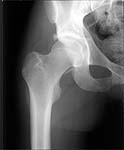

22 yrs man , semiprofessional( he earn some money from playing) basketball player got suffered in car accident.He had hip joint posterior luxation ( Pipkin 4) with little acetabular roof fragments ( nondisplaced) and anterosuperior abruption fracture of the head of the femur.

Additional injuries were severe face wounds. Emergency manipulations were reposition of the hip luxation under the radiologic control and wounds care. After reposition the CT scan was made. We found 2x3cm wide and 0.5 thick OCH fragment outside the joint surfaces , under the caput. The traction was applied.

I don't know what chance ORIF has of working. I'm not sure you can get the piece to heal very well. It's markedly displaced, almost certainly avascular. It looks pretty thin.

i'd like to see post reduction x-rays to assess congruency of the reduction including AP & both Judet views. If the fragment is truly small, and extra-articular and the joint is stable, probably nothing needs to be done with the fragment, but i'd like more views! thanks

Here are the missing postreduction views.